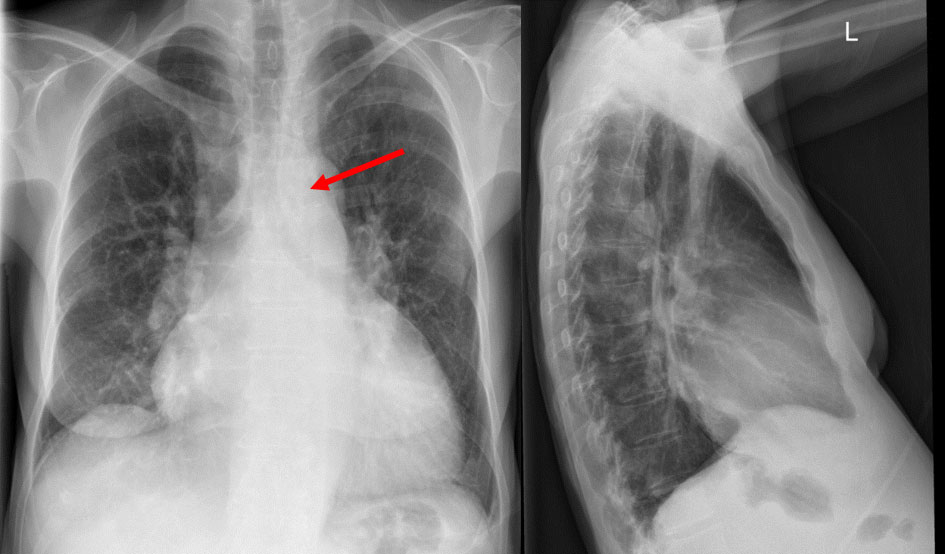

Besides distinct right heart enlargement, pronounced pulmonary artery dilatation is visible on a postero-anterior chest x-ray (fig. 4). Furthermore, the so-called Hampton (sign of previous infarction) and Westermark (areas of hypoperfusion) signs can be observed.

Figure 4 Chest x-ray. Arrow: prominent pulmonary artery. (Courtesy of Prof. T. Frauenfelder.)